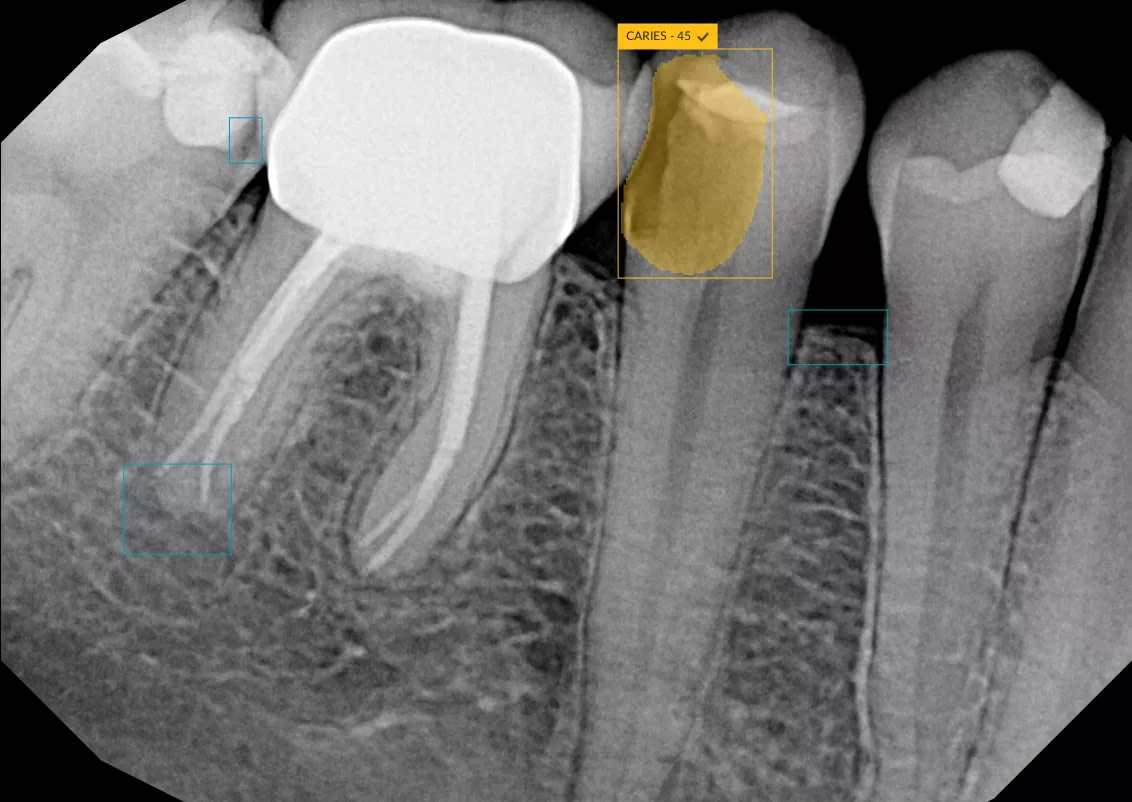

- Automatically file and organize radiographs

- Detect caries, calculus, bone loss, and other pathologies